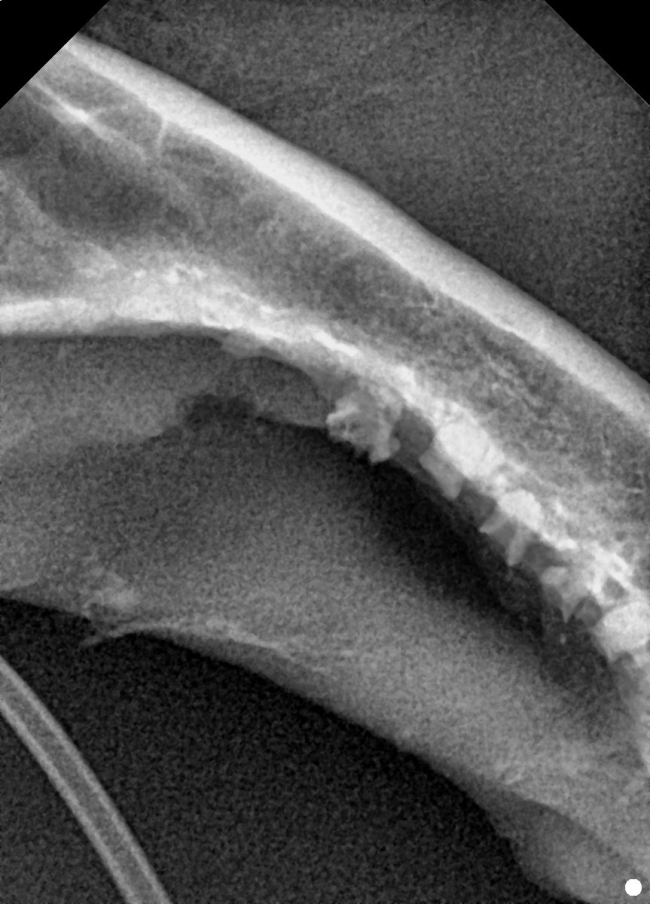

치료중 대상묘

치료완료후